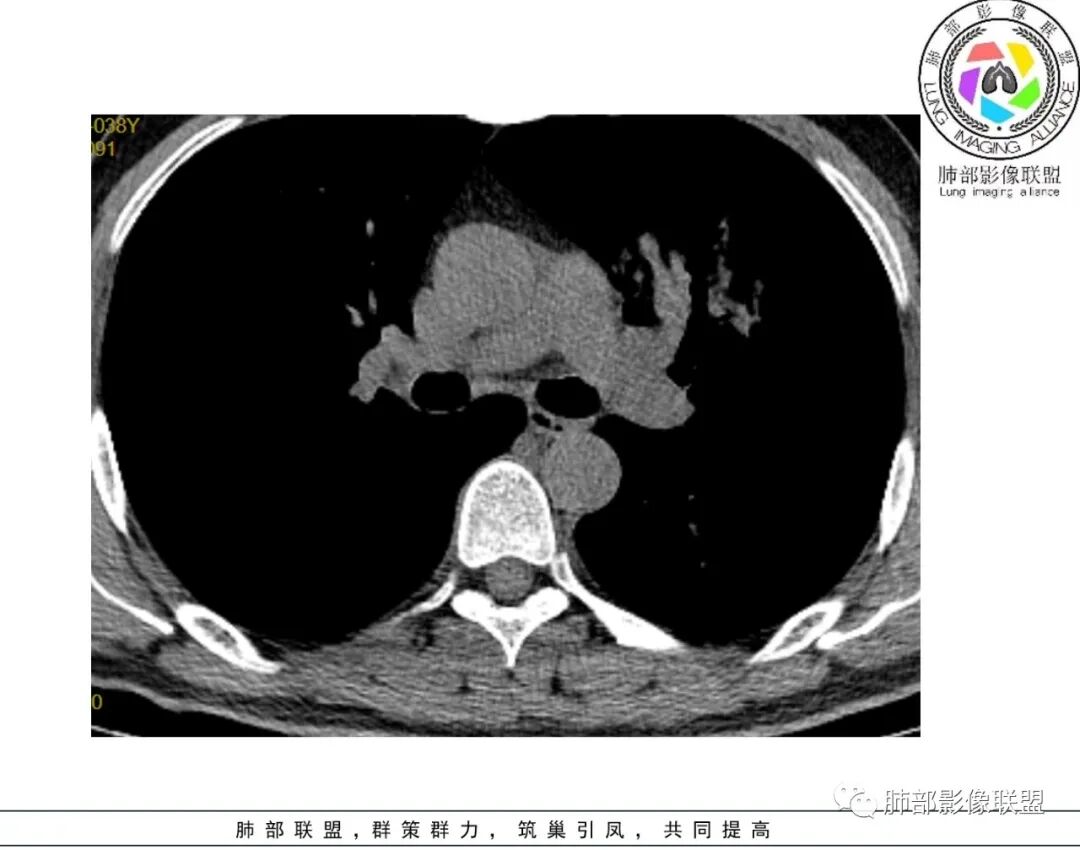

病例资料:男性,48 岁。因“反复咳嗽、咳痰1 周,加重伴气促2天”于2018 年9 月7 日入院。外院胸部CT示右肺炎,经治疗后无好转,来我院急查血常规示:白细胞9.2× 10^9 /L,N% 84.9%。超敏CRP:462.52mg/L。降钙素原>100ng/ml。葡萄糖19.6mmol/L。血酮体(+)。查体: 体温:40.2℃,呼吸:32次/分,脉搏:164次/分,血压:100/

38mmHg( 多巴胺维持) 。呼吸机辅助呼吸,双下肺可闻及较多湿啰音,心率齐,未闻及杂音。诊断:重症肺炎呼吸衰竭、感染性休克、2型糖尿病并酮症酸中毒。

本病例肺部病灶累及双肺,以右中上肺的浸润状团块影为主要表现,伴有双肺结节影及胸腔积液,后期局部空洞形成。类鼻疽肺部病灶吸收缓慢,发病第22天时肺部病灶仍无明显变化,发病第65天时肺部病灶仍未完全吸收。本例患者出院后1个半月仍抗感染治疗,经随访无复发表现。